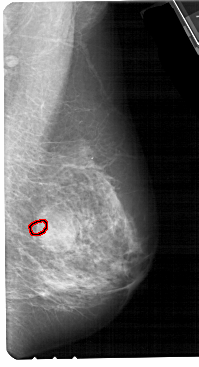

A_1705_1.LEFT_MLO

LEFT_MLO LINES 5491 PIXELS_PER_LINE 2701 BITS_PER_PIXEL 12 RESOLUTION 43.5 NON_OVERLAY

FILE: A_1705_1.RIGHT_MLO.OVERLAY

TOTAL_ABNORMALITIES 1

ABNORMALITY 1

LESION_TYPE CALCIFICATION TYPE PLEOMORPHIC DISTRIBUTION CLUSTERED

ASSESSMENT 4

SUBTLETY 2

PATHOLOGY BENIGN

TOTAL_OUTLINES 1

BOUNDARY